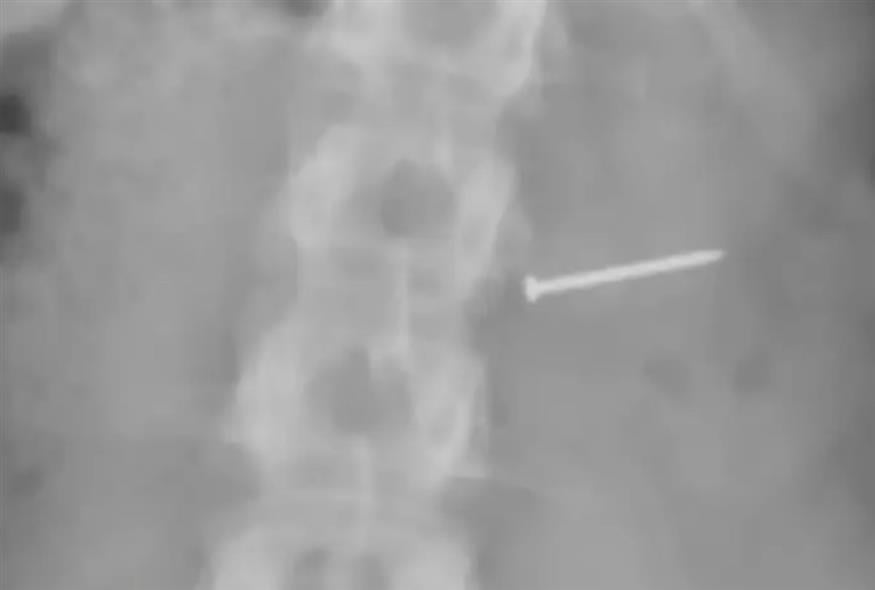

«Όταν κατάπια, ένιωσα κάτι στον λαιμό μου που κάπως κόλλησε. Νόμιζα ότι ήταν ξηρός καρπός αλλά και πάλι ένιωθα περίεργα. Πήγα στο νοσοκομείο για να βγάλω μια ακτινογραφία και όταν βγήκαν τα αποτελέσματα, σοκαρίστηκα. Είχα καταπιεί ένα καρφί.

Η Μπάκλεϊ κατέθεσε αγωγή ζητώντας αποζημίωση καθώς σύμφωνα με την ίδια, είχε υποστεί σοβαρούς και μόνιμους τραυματισμούς στον λαιμό, τα άκρα, το νευρικό σύστημα, απώλεια σωματικών λειτουργιών και νευρολογική βλάβη. Όπως μάλιστα υποστήριξε, το περιστατικό αυτό της στέρησε τη δυνατότητα να αποκτήσει άλλο παιδί.